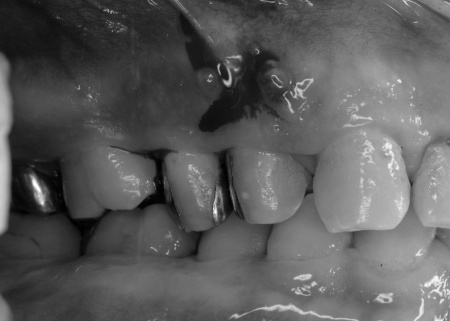

拝見したところ、右上奥歯の歯ぐきが腫れ、出血も見られました。

また、右下の奥歯3本は歯周病が重度まで進行していました。

続いて歯周治療として、歯ぐきの上に付着している歯石を専用の器具で除去し、歯ぐきの炎症を改善しました。

歯ぐきの状態が落ち着いたことを確認してから、再生療法に進みます。